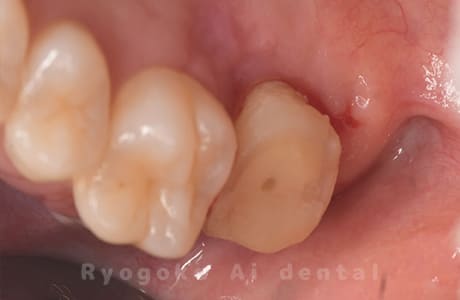

Case04

- 原因

- 慢性根尖性歯周炎

- 治療期間

- 3ヶ月

- 治療内容

- マイクロエンド

- 治療費用

- 121,000円

噛むと痛みが出る、とのことで来院した患者様です。他院での根管治療を終えてましたが、根尖病変を認めるため、マイクロエンドを行いました。